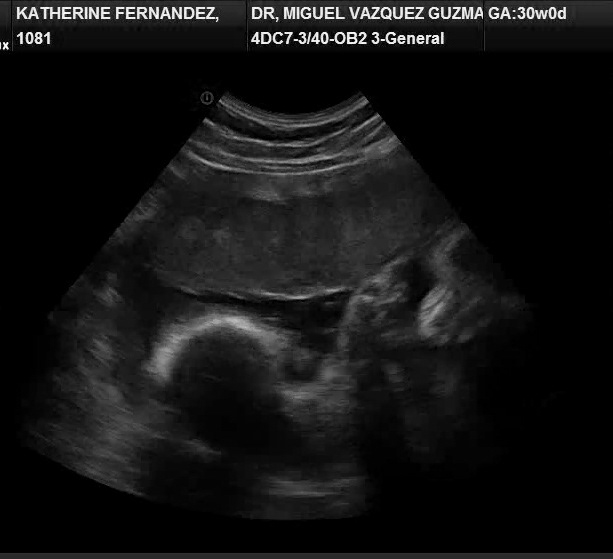

El ginecólogo obstetra ¿Miguel como está? Muy bien y tú, según veo en el monitor, lista para parir, me responde. ¿Cómo? esto estaba programado, pero yo no sentía dolores, que era lo que esperaba, si llegaba el momento. Yo primeriza con un ser dentro que nunca se puso en posición, no lograba entender que la sensación de presión en el abdomen era producto de las contracciones. Así que el #bebe ya estaba listo para salir.